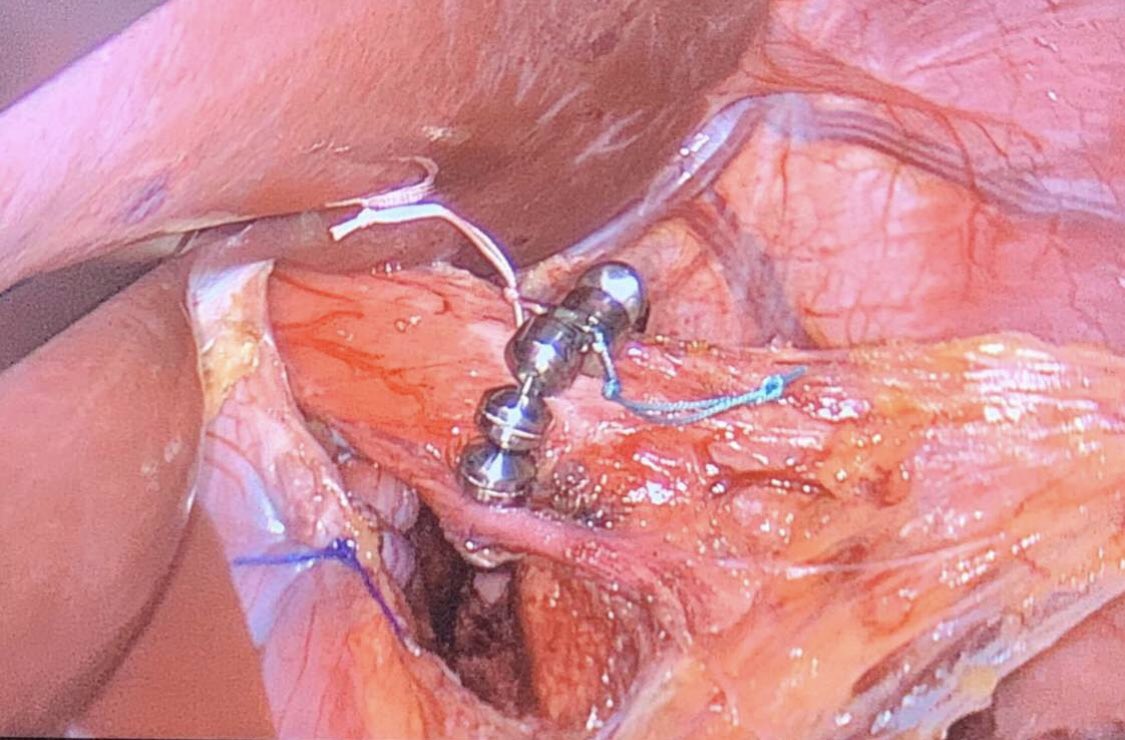

حلقة او سوار معدني يتكون من حبيبات مصنوعة من المغناطيس ومغلفة ومتصله بسلك من التيتانيوم يسمح لها بالتمدد (لمرور الطعام الى المعدة) والانقباض (لمنع ارتجاع الحمض من المعدة الى المريء)

عملية تجرى بمنظار البطن بفتحات صغيرة تحت التخدير العام وتستغرق حوالي الساعة او الساعتين

ويتم خلالها إصلاح فتق الحجاب الحاجز ان وجد ووضع سوار اللينكس أسفل المريء لتقوية عضلات الصمام